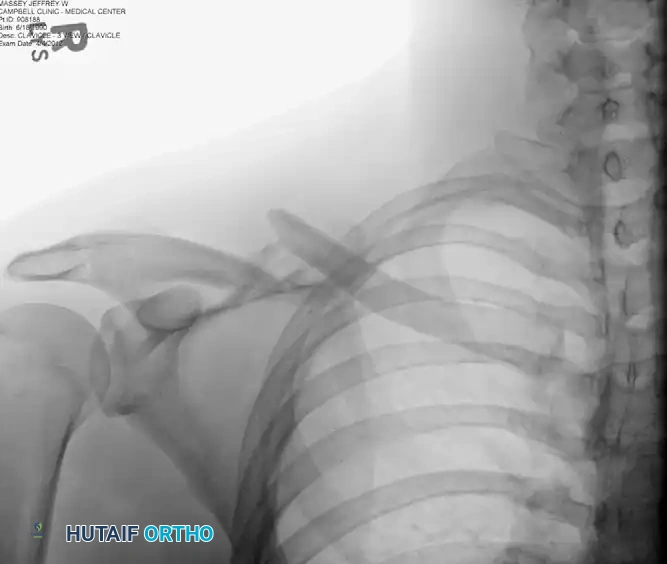

Figure: Preoperative radiograph demonstrating a displaced midshaft clavicular fracture suitable for superior plating.

Standard evaluation requires an anteroposterior (AP) view and a 15- to 20-degree cephalad tilt view. The cephalad view projects the clavicle above the thoracic cage, providing a clear assessment of superior/inferior displacement and shortening. 3D CT reconstruction is rarely required for midshaft fractures but is invaluable for medial or lateral third fractures with intra-articular extension.